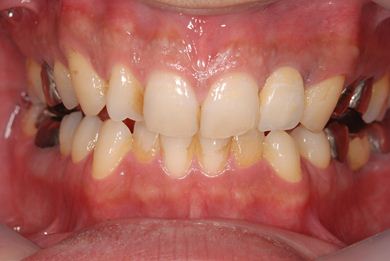

インプラントの症例写真 IMPLANT

抜歯即日スピードインプラント治療

| 性別/年齢 | 男性 / 36歳 | ||||||||||||||||||||||||||||||||

| 主訴 | 前歯が折れていてないので、インプラント治療を希望。 | ||||||||||||||||||||||||||||||||

| 治療内容 | インプラント1本(抜歯即日スピードインプラント)、ハイブリッドセラミッククラウン1本 | ||||||||||||||||||||||||||||||||

| 総治療費 | 257,250円 | ||||||||||||||||||||||||||||||||

| 治療期間 | 7ヶ月 |